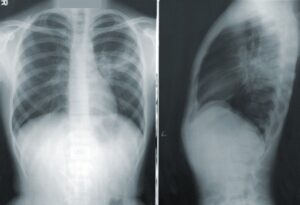

治療法として上がっているのは、まず病院それもレントゲン設備が整ってる環境がある病院で、レントゲン検査を行う事です。

会社勤めの方ですと、年に一度健康診断を受ける事が義務付けられてますが、それ以外で日常生活において胸の痛みが出たら即レントゲンを受けるべきです。

レントゲンで肺が真っ白さが、出た場合は気胸となります。

こぅなった場合は、即治療になるでしょう?